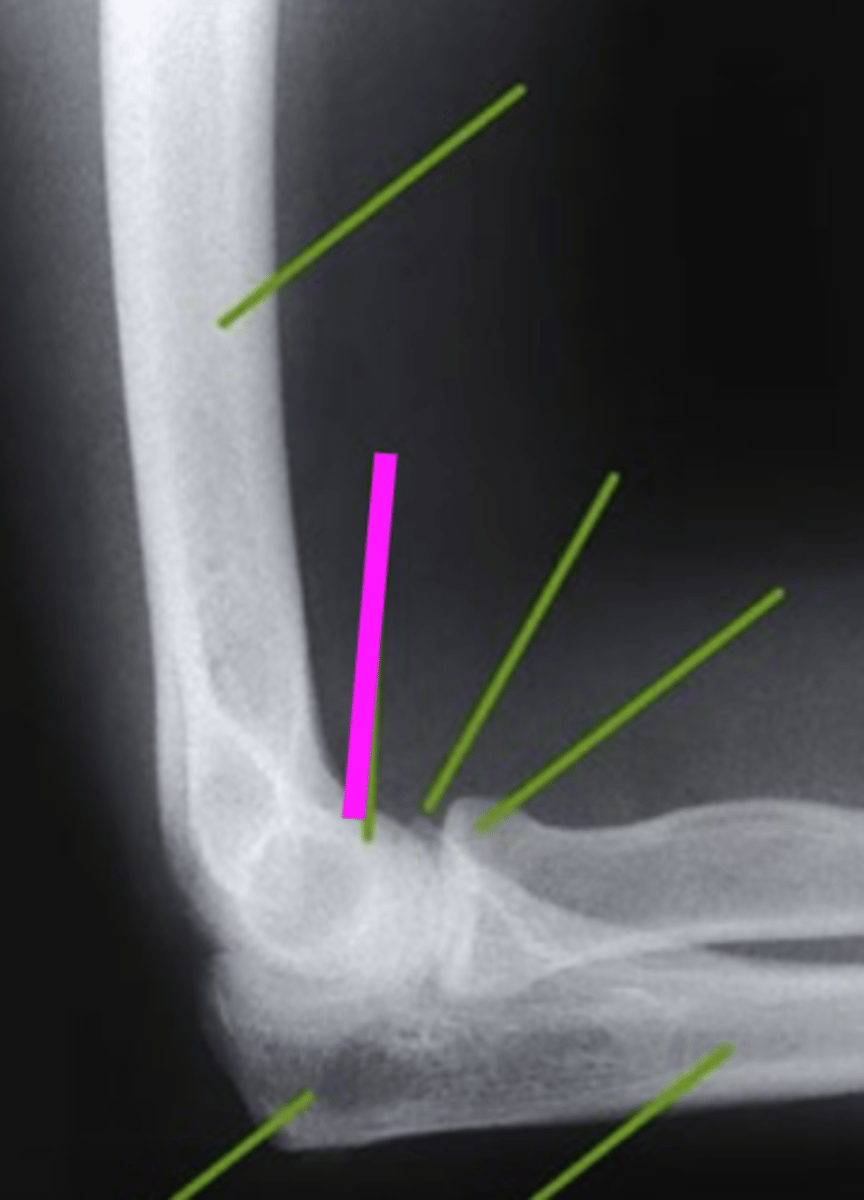

Lateral Elbow

what view is this

humerus

what does the pink line point to?

trochlear sulcus

coronoid process of olecranon

radial head

olecranon process

ulna